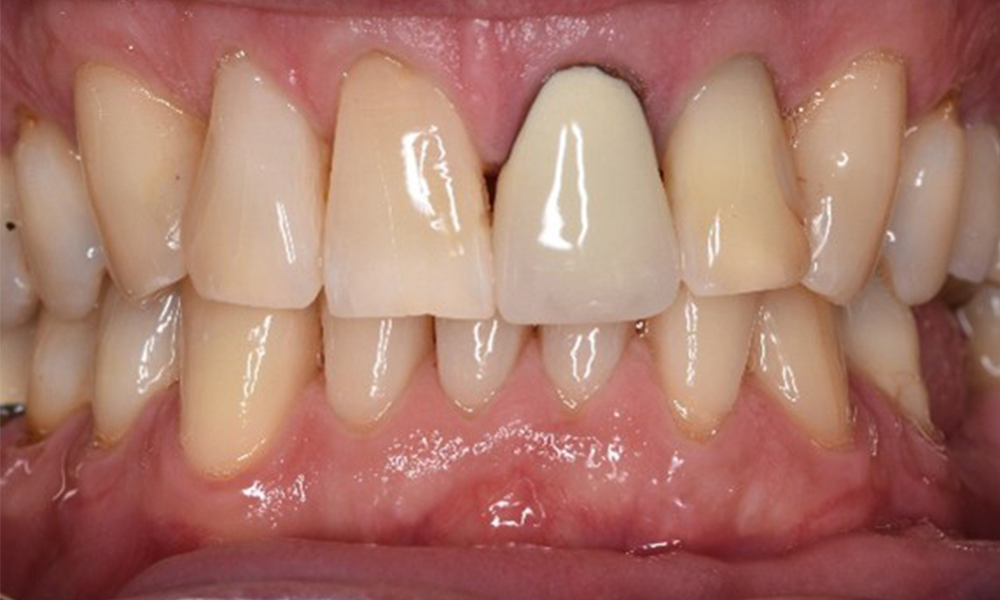

Преден изглед на зъбите (горна и долна челюст)

Изглед отпред